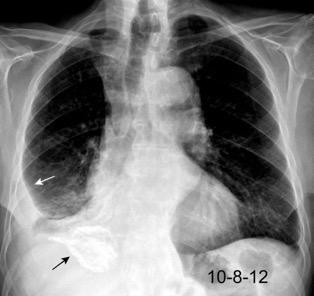

Tromboembolismo pulmonar Diafragma elevado 20%

Consolidación por Infarto pulmonar. (TEP)

Borramiento del hemidiafragma derecho

“Visible en toda su longitud en lateral”.